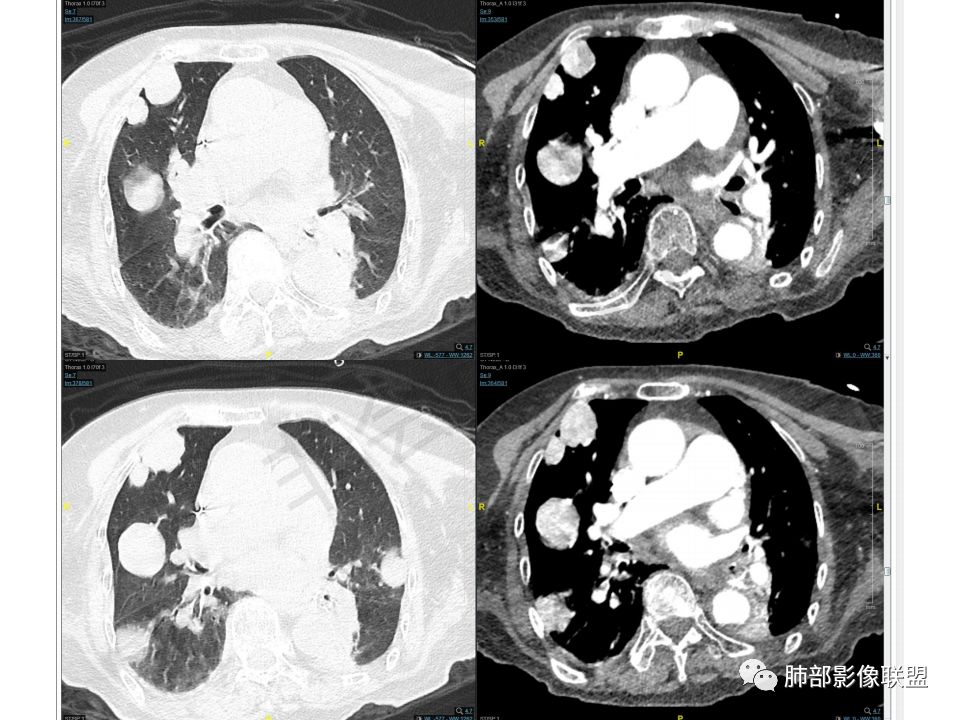

老年女性,两肺多发球形结节,边缘光滑,部分位于胸膜下,纵隔淋巴结肿大不明显,胸水少量,增强后强化明显,考虑转移,肉瘤转移的可能,补充下病史。气管内新生物,是不是二元,息肉或肿瘤

老年女性,间断咯血两年。影像:气管内带蒂结节,边缘光滑明显强化。左肺下叶背段支气管截断,远端不张。两肺散在大小不等结节及磨玻璃影,明显强化,磨玻璃影考虑合并出血可能。纵隔多发淋巴结肿大,两侧支气管受压。综合考虑:肺癌伴两肺转移。原发气管结节还是左肺下叶背段?腺样囊性癌?类癌?

老年女性,慢性病程。两肺多发类圆形结节、肿块,边缘光滑,胸膜下分布为主,显著强化,考虑转移瘤。气管内肿块,边缘光整,强化方式与肺内肿块一致,一元考虑气管肉瘤并双肺转移。

双肺多发大小不等结块,边缘光滑,随机分布,部分融合,密度不均匀,增强后可见不均匀明显强化(富血供),肺门及纵隔淋巴结肿大融合,老年女性,综合考虑转移瘤,建议查全身脏器,必要时Pet-CT, 鉴别小细胞肺癌。

两肺结节胸膜下,边缘光滑,强化与气管内病灶一致

从强化的一致性、形态的一致性,倾向于气管、肺内病灶一元论

强化这么丰富的肿瘤真不多见,形态也一致